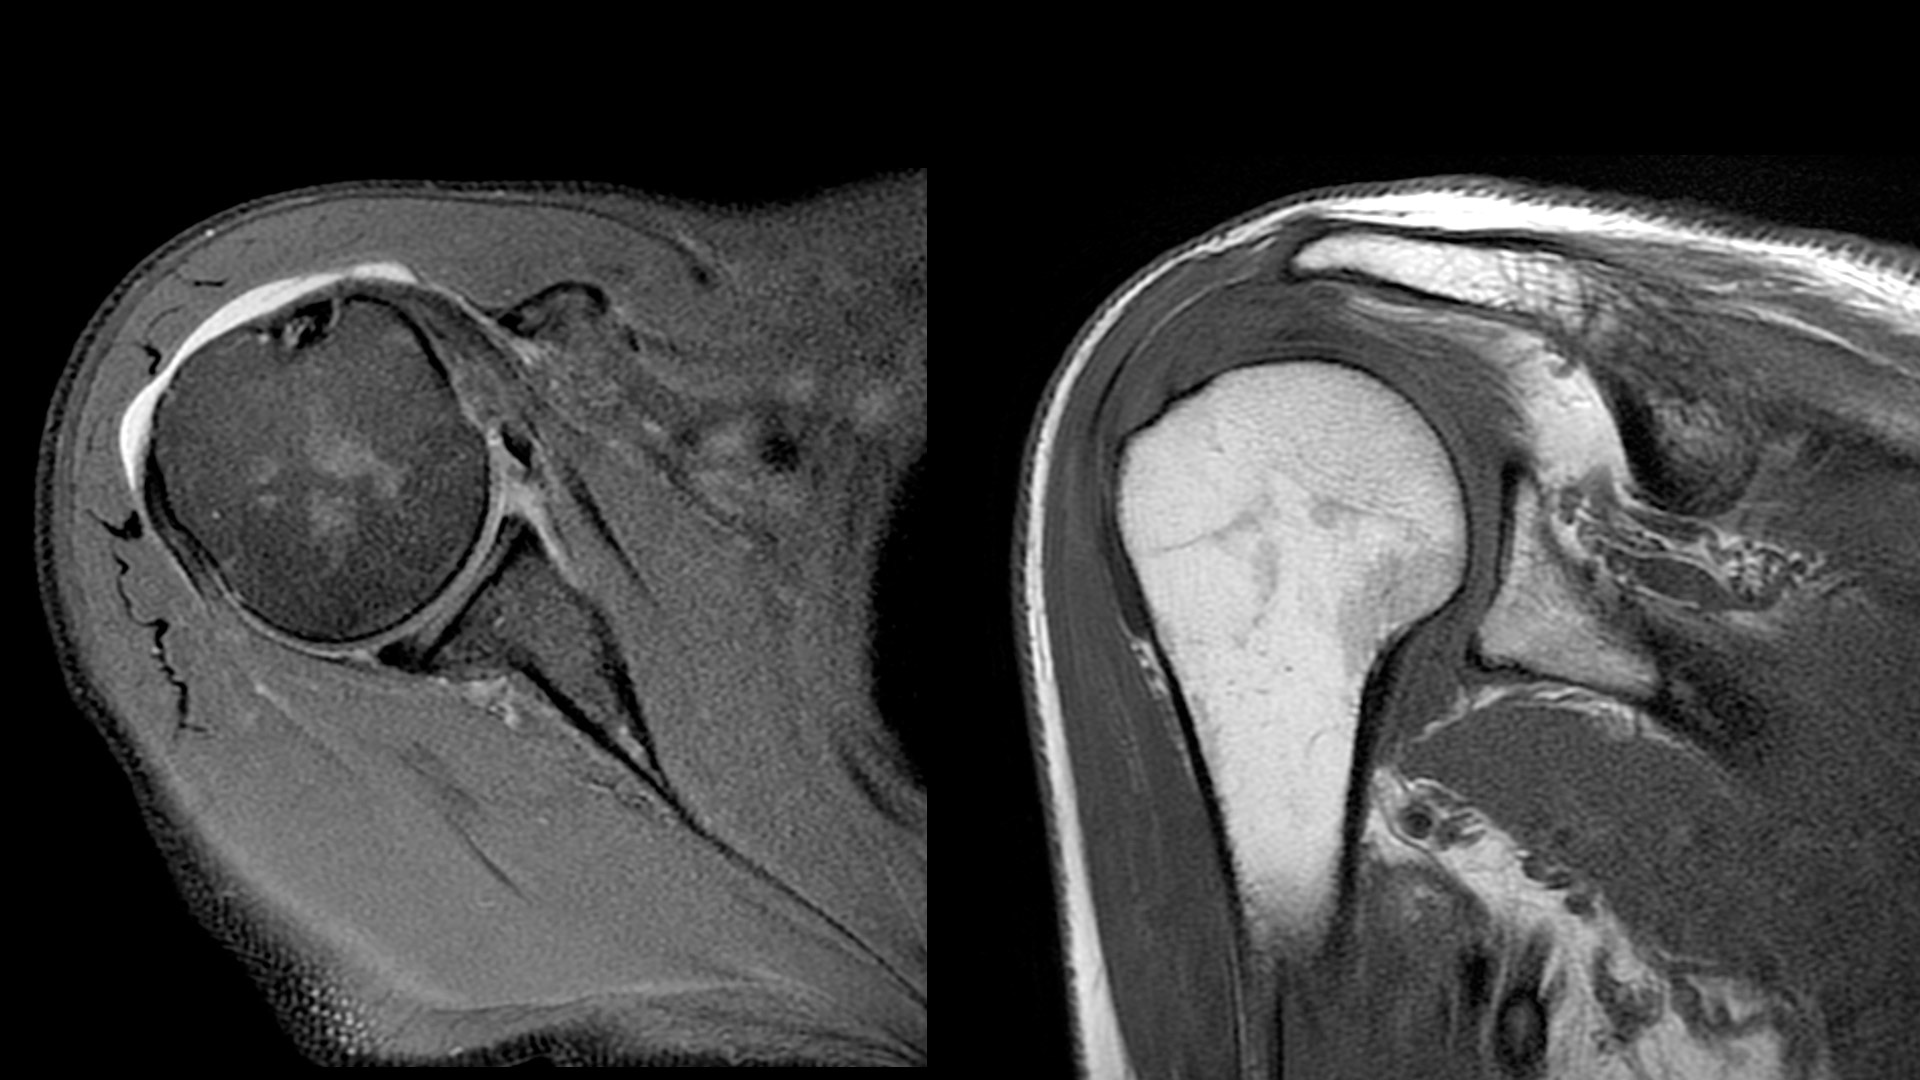

Clinical excellence

Coil flexibility makes it easier to get closer to the patient, providing more coverage compared to other coils